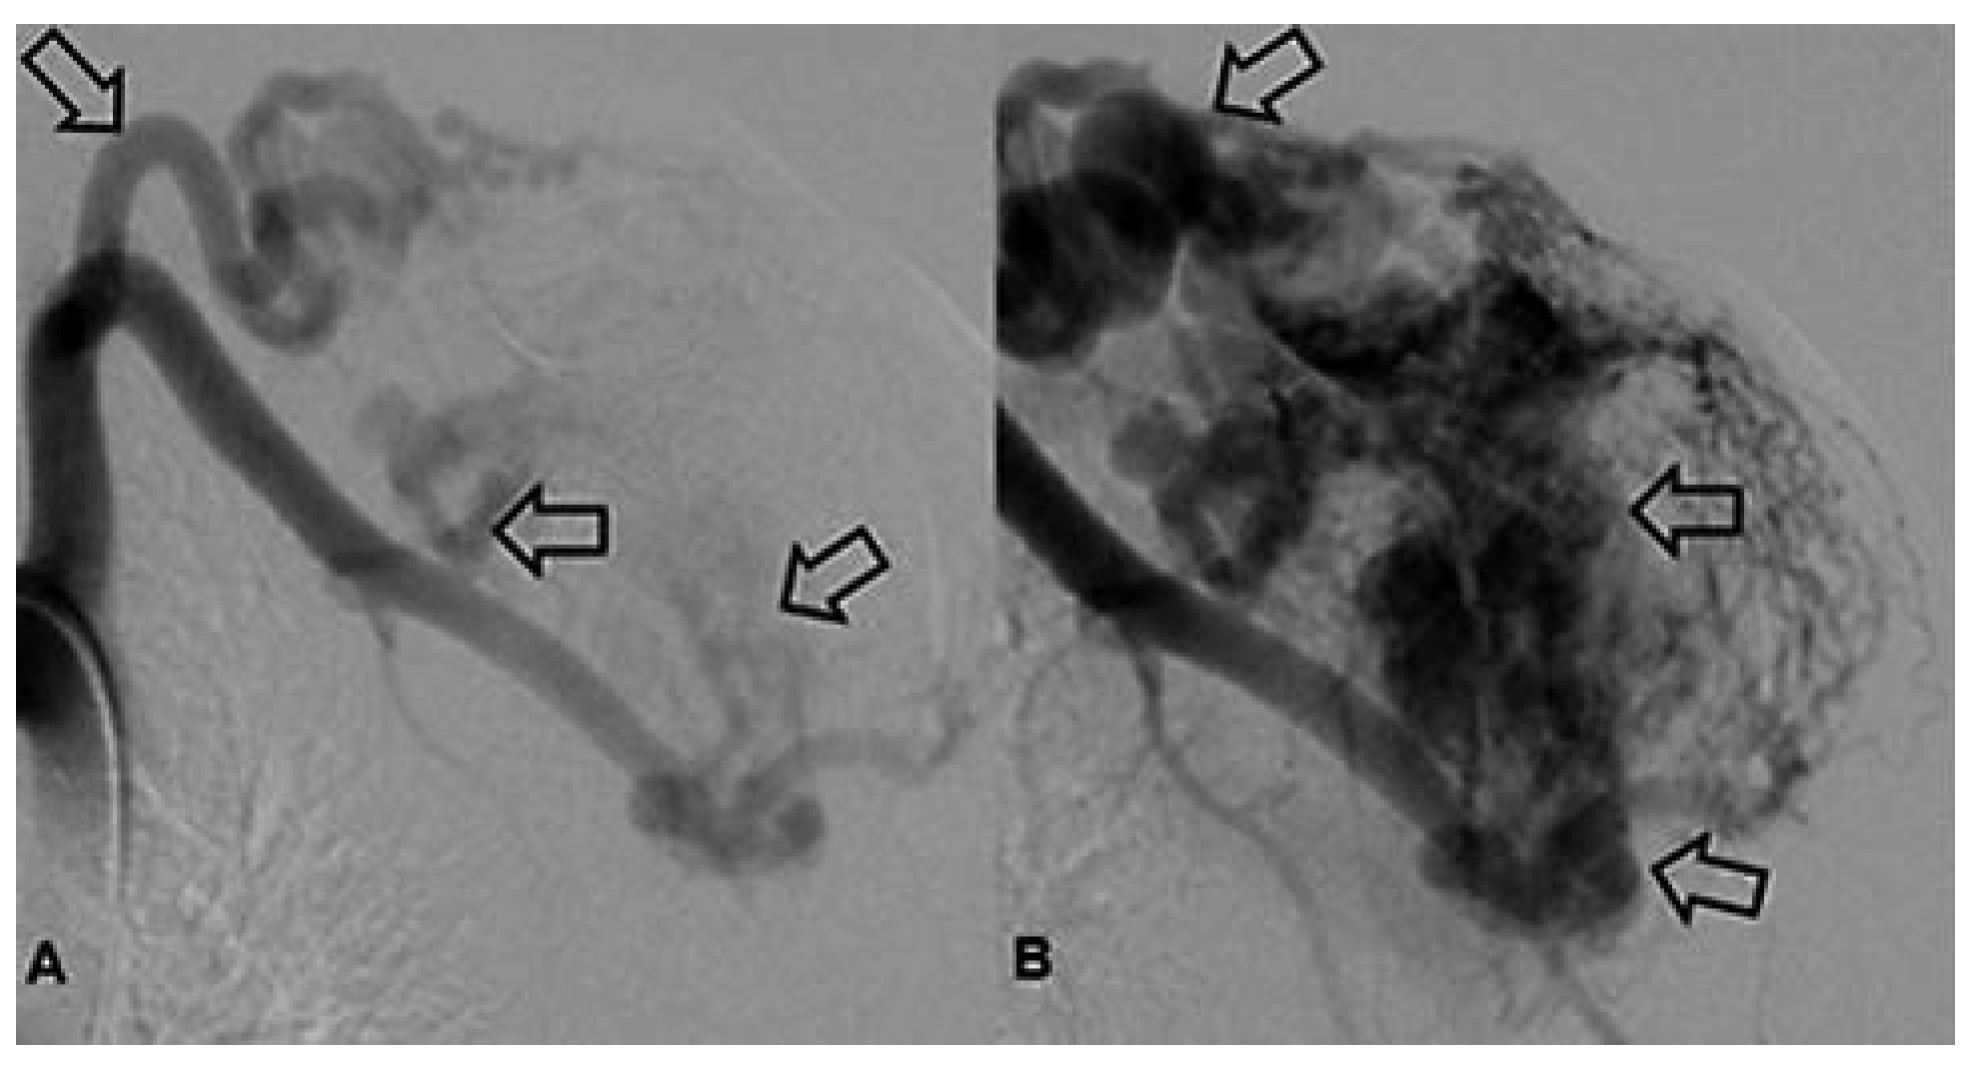

Arteriovenöse Malformation